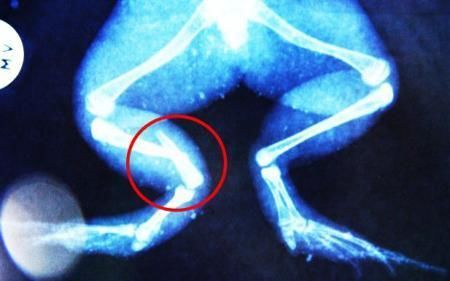

環(huán)球網(wǎng)4月2日報道 據(jù)《每日郵報》報道,上個月,南非大牛蛙布魯萊的右小腿被鄰居家的一只狗咬到,導(dǎo)致粉碎性骨折,現(xiàn)在經(jīng)過2個小時的手術(shù),它的斷腿已經(jīng)被接上,它也因此成為有史以來第一只通過外科手術(shù)用鋼針接上斷腿的青蛙。

布魯萊的主人,居住在南非約翰內(nèi)斯堡附近的62歲的安妮·米恩斯說:“我對這只青蛙如此關(guān)心,人們一定認(rèn)為我瘋了,但是我無法眼睜睜看著它那么痛苦。青蛙因其靈活的腿腳而著稱,一想到布魯萊的腿里要留下一個薄金屬片,我就感到心痛。然而我知道,如果不進行手術(shù),布魯萊以后就沒辦法動彈了。因此我匆匆趕到獸醫(yī)那里,央求他給這只可憐的青蛙動手術(shù)。這位獸醫(yī)整天救助小貓小狗,他很難理解為什么我這么擔(dān)心一只青蛙,但是最終他還是答應(yīng)了給布魯萊做手術(shù)。手術(shù)后是幾個小時的焦急等待,我們希望它能快快蘇醒過來。不過現(xiàn)在它的傷口已經(jīng)愈合,又能在花園里跳來跳去了。X光照射顯示,它會恢復(fù)的跟以前一樣。”

野生生物專家安妮經(jīng)常為學(xué)校寫教材,她認(rèn)為這是人類第一次通過手術(shù)給一只青蛙接斷腿。在手術(shù)開始階段,獸醫(yī)把少量給狗用的麻醉藥注入到這只青蛙體內(nèi),讓它失去知覺。然后他在布魯萊的斷腿上切開一個小口,把一根小鋼針植入腿里。最后獸醫(yī)給它縫了9針,把切口縫合在一起。僅僅幾周后,布魯萊就能在安妮家附近活動了。這只青蛙大約已有25歲,主要以嚙齒動物、蛇和其他青蛙為食。布魯萊所屬的牛蛙種群正在不斷減小,目前只能在非洲南部的濕地里才能看到這種青蛙。